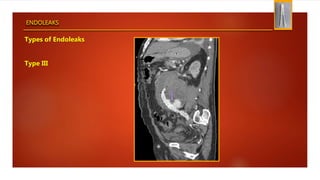

Types of Endoleaks

Type III